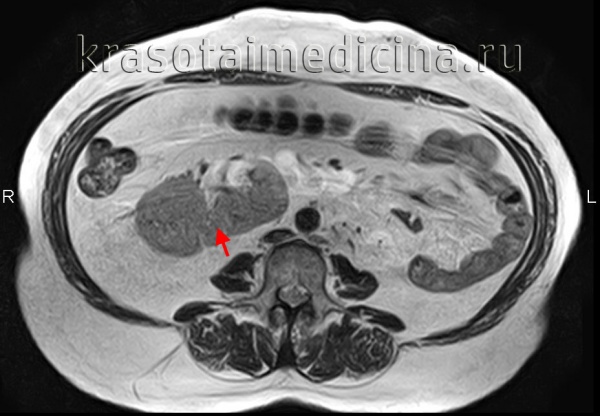

3. КТ при подковообразной почке:

• КТ с контрастированием:

о Позволяет определить структурные аномалии:

- Степень и локализация сращения: срединное или боковое сращение

- Степень мальротации почки

- Изменения почечной паренхимы (например, рубцевание, поликистоз)

- Аномалии собирательной системы (например, удвоение системы, гидронефроз)

о Позволяет дифференцировать структуру перешейка (фиброзная или нормальная паренхима)

- КТ почти всегда позволяет визуализировать функционирующую паренхиму в перешейке